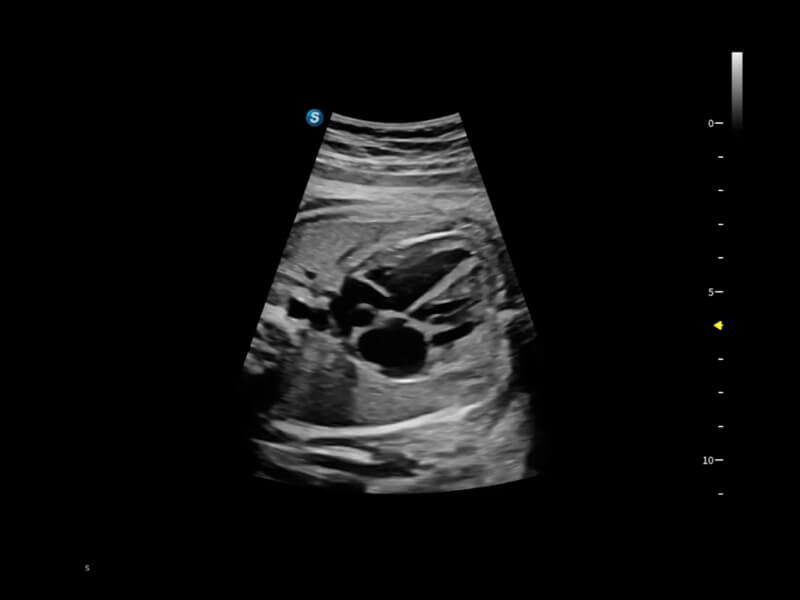

作為開(kāi)立醫(yī)療全新打造的超高端旗艦超聲產(chǎn)品,從探頭抬起喚醒開(kāi)啟掃查到多維探頭發(fā)射接收,通過(guò)先進(jìn)的場(chǎng)成像發(fā)射、自適應(yīng)聚合重建等技術(shù),基于RF Data原始射頻數(shù)據(jù)在圖像生成、高端功能等方面實(shí)現(xiàn)突破,為婦產(chǎn)科、兒科提供全方位臨床解決方案。

夢(mèng)溪?P80以“關(guān)愛(ài)女性”為基石,提供全方位的解決方案,量身定制以滿(mǎn)足女性的健康需求,涵蓋婦科、生殖健康檢查、產(chǎn)前篩查及產(chǎn)后康復(fù)等領(lǐng)域。